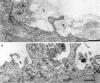

Results: An African American man had EBS since early infancy, and progressive muscle weakness, hyperCKemia, and myasthenic symptoms refractory to therapy since age 3 years. Eventually he became motionless and died at age 42 years. At age 15 years, he had a marked EMG decrement, and a reduced miniature endplate potential amplitude. The myopathy was associated with dislocated muscle fiber organelles, structurally abnormal nuclei, focal plasmalemmal defects, and focal calcium ingress into muscle fibers. The neuromuscular junctions showed destruction of the junctional folds, and remodeling. Mutation analysis demonstrated a known p.Arg2319X and a novel c.12043dupG mutation in PLEC1. The EBS-MD-MyS patient reported in 1999 also carried c.12043dupG and a novel p.Gln2057X mutation. The novel mutations were absent in 200 Caucasian and 100 African American subjects.

Conclusions: The MyS in plectinopathy is attributed to destruction of the junctional folds and the myopathy to defective anchoring of muscle fiber organelles and defects in sarcolemmal integrity.